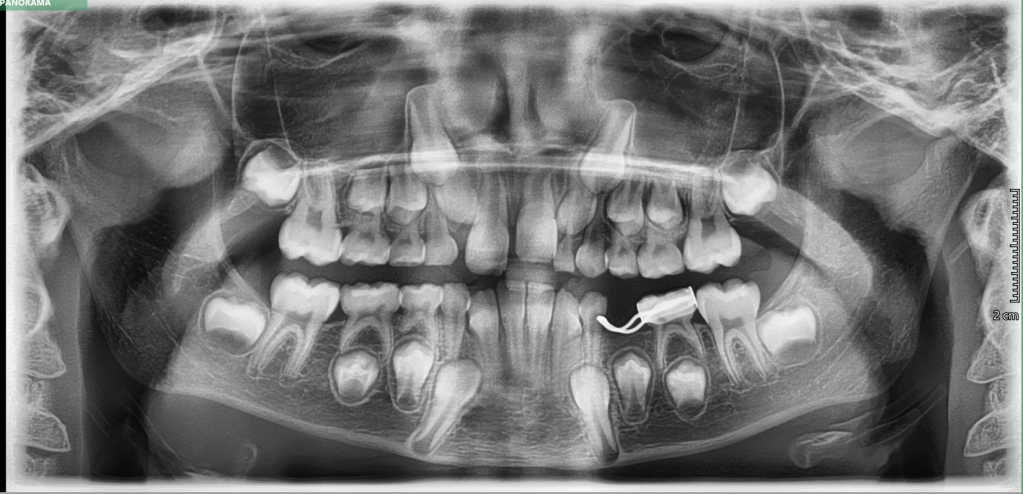

This appliance is commonly used in children and teenagers to widen the upper jaw (maxilla) when it is too narrow. A narrow jaw can cause problems like crowding of teeth, crossbites, and difficulty breathing through the nose. Usually diagnosis is done using an OPG radiograph.